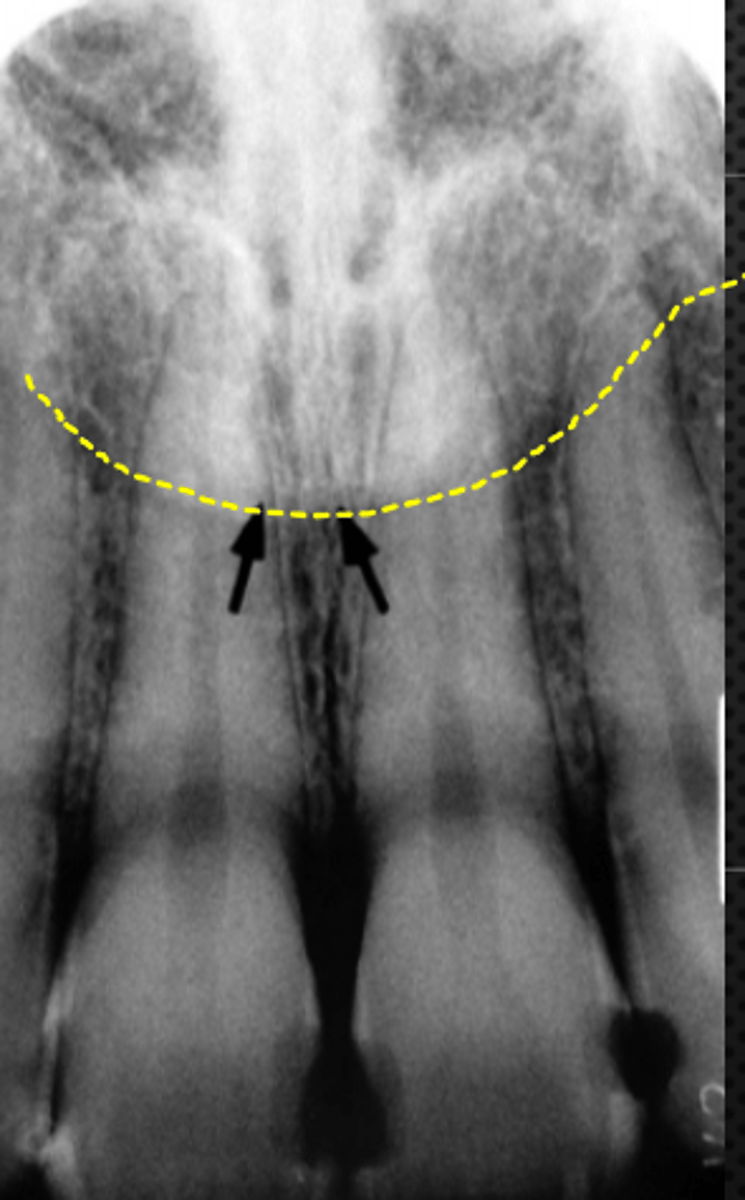

Floor of nasal cavity

Identify the structure

<p>Identify the structure</p>

6